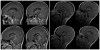

Object: Thalamopeduncular tumors arise at the junction of the inferior thalamus and cerebral peduncle and present with a common clinical syndrome of progressive spastic hemiparesis. Pathologically, these lesions are usually juvenile pilocytic astrocytomas and are best treated with resection with the intent to cure. The goals of this study are to define a common clinical syndrome produced by thalamopeduncular tumors and to discuss imaging characteristics as well as surgical adjuncts, intraoperative nuances, and postoperative complications relating to the resection of these neoplasms.

Results: Pilocytic astrocytoma was the pathological diagnosis in 9 cases, and the other was fibrillary astrocytoma. Seven of 9 pilocytic astrocytomas were completely resected. Radical surgery was avoided in 1 child after DT imaging revealed that the corticospinal tract (CST) coursed through the center of the tumor, consistent with the infiltrative nature of fibrillary astrocytoma as identified by stereotactic biopsy. In 8 patients, tractography served as an important adjunct for designing a surgical approach that spared the CST. In 6 cases the CSTs were pushed anterolaterally, making a transsylvian approach a poor choice, as was evidenced by the first patient in the series, who underwent operation prior to the advent of tractography, and who awoke with a dense contralateral hemiparesis. Thus, subsequent patients with this deviation pattern underwent a transcortical approach via the middle temporal gyrus. One patient exhibited medial deviation of the tracts and another had lateral deviation, facilitating a transtemporal and a transfrontal approach, respectively.

Conclusions: The thalamopeduncular syndrome of progressive spastic hemiparesis presenting in children with or without symptoms of headache should alert the examiner to the possibility of a tumoral involvement of CSTs. Preoperative tractography is a useful adjunct to surgical planning in tumors that displace motor pathways. Gross-total resection of pilocytic astrocytomas usually results in cure, and therefore should be entertained when developing a treatment strategy for thalamopeduncular tumors of childhood.